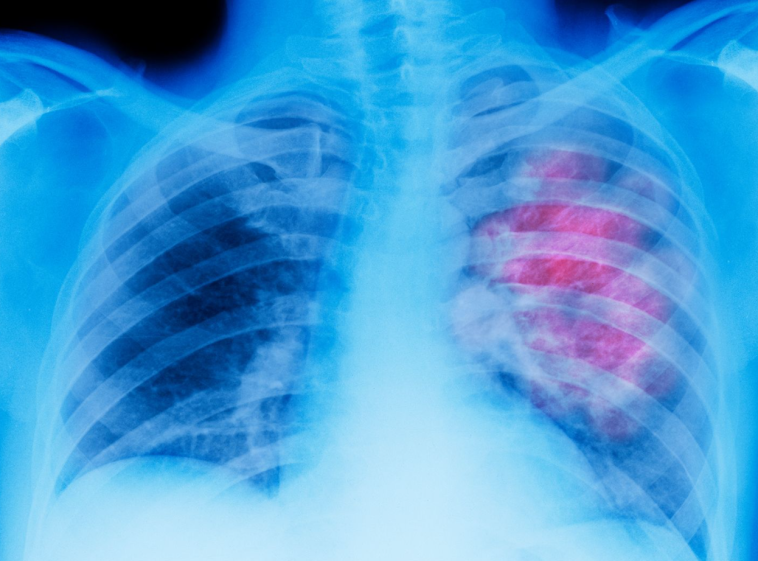

Οι καπνιστές αποτελούν ομάδα υψηλού κινδύνου για την ανάπτυξη σοβαρών πνευμονικών παθήσεων, όπως ο καρκίνος του πνεύμονα και η χρόνια αποφρακτική πνευμονοπάθεια (ΧΑΠ). Μία νέα μελέτη που δημοσιεύθηκε πρόσφατα αναδεικνύει την αξία της ετήσιας αξονικής τομογραφίας θώρακα σε καπνιστές, επισημαίνοντας ότι η έγκαιρη διάγνωση μπορεί να σώσει ζωές.